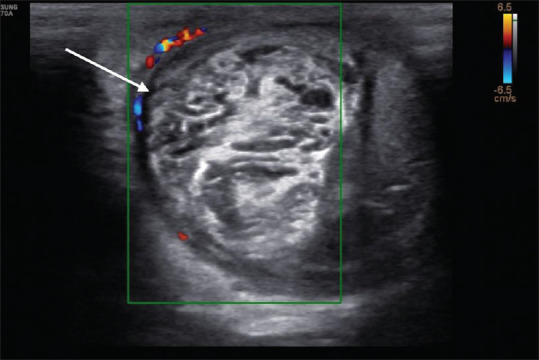

Testicular torsion is an emergency clinical situation. It is rarely seen associated with ureterocele. We presented a case report where a 15-year-old adolescent boy presented with severe testicular and vague abdominal pain was found on imaging to have testicular torsion and ureterocele. Ultrasonography Doppler and computed tomography imaging are being described.

睾丸扭转是一种紧急的临床情况。它很少与输尿管囊肿合并。我们提出一个病例报告,一个15岁的青春期男孩表现为严重的睾丸和模糊腹痛,在影像学上发现有睾丸扭转和输尿管膨出。介绍了超声多普勒和计算机断层成像。